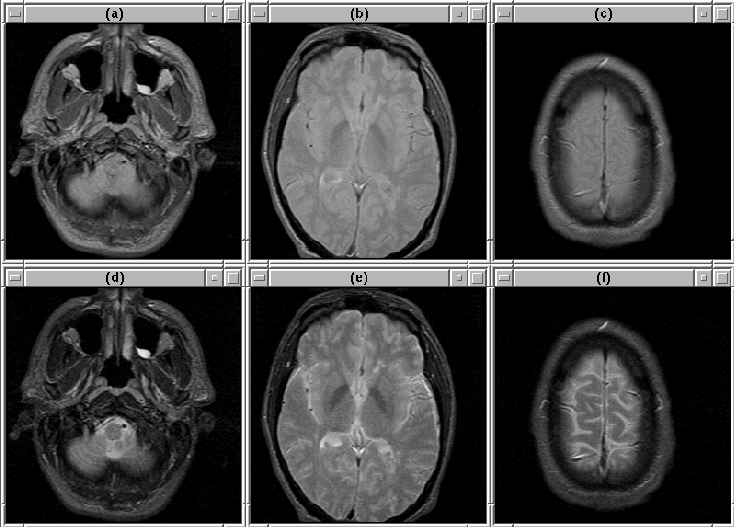

Figure 8.4 shows slices selected from Data Set 4. The lower slices contain bright anomalies, that might be due to clogged sinuses or dental work, in regions outside the brain. These anomilies could confuse the intracranial boundary detection algorithm. Other bright anomilies, perhaps fat deposits, appear in the forehead area of the patient (see slice 12).

Figure 8.4: Selected slices from MRI Data Set 4. (Top) PD-weighted. (Bottom) T2-weighted. (a), (d) Slice 2. (b), (e) Slice 12. (c), (f) Slice 24.

Figure 8.5 shows selected image slices from Data Set 5. Except for some obvious partial volume effects in slice 2, there are no remarkable features in the volume.

Figure 8.5: Selected slices from MRI Data Set 5. (Top) PD-weighted. (Bottom) T2-weighted. (a), (d) Slice 2. (b), (e) Slice 12. (c), (f) Slice 24.